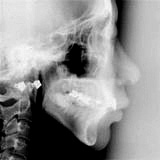

実は今、夫婦で真剣に取り組んでいるのは矯正治療です。

今までも多くの方を治療させて頂いているので、「何を今更・・」とお思いでしょうが、今ま

では成人を対象にしていたわけです。歯周病の治療を真剣にやればやるほど「磨けない」場所へ

の対応が必要になりました。患者さんが本気で治したいと思っていて、ブラッシングの技術も上

手なのに、歯並びが悪いために絶対に磨けない場所があると、まじめに定期検診に来て頂いても

徐々に悪化していきます。そのまま見ていてもいつか「抜歯」するしか方法がありません。そう

いう長期的な経験から、成人の歯列矯正の必要性を感じて治療を始めたわけです。

矯正治療というのは子供をターゲットにするのが一般的です。でも、うちの病院は歯周病とイ

条件を整えてあげると装置すら必要じゃない場合もあります。これから、数回シリーズで矯正治

療のホントのところを書いてみようかなと思います。

今回は矯正治療について一般的なところをお話ししたいと思いま

す。まずはその費用について。矯正治療というと「高い!」とお考え

の方が多いと思います。確かに80〜100万円掛かりますので、安い

とは言えません。しかし、インプラントを3本入れるだけで90万円

を超えます。人間の歯は28(32)本あるのに、たった3本で矯正治

療よりも高額になってしまうんです。そういう風に言うと矯正が安い

ように思うかもしれませんが、やはり安くはありません。「インプラ

ントもイヤだし、矯正もイヤ!」と思う方は多いでしょう。じゃあ、

なぜインプラントが必要になるのでしょう?それは歯が無くなってし

まったからです。なぜ歯が無くなってしまうのでしょう?主に二つの理由があります。一つは歯

周病のために歯が脱落する場合、もう一つは虫歯が進行して、歯が折れてしまったり、歯の根の

病気で痛みが出て抜歯された場合です。歯周病も虫歯も歯並びが良くて歯を磨きやすければずい

ぶんと進行を食い止めることができます。この二つを減らすことにより、将来入れ歯やインプラ

ントをしないで一生を過ごす可能性が高くなります。今の日本も似た状況になってきましたが、